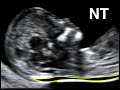

The Thick Nuchal Translucency

NT (nuchal translucency) and NF (nuchal fold) U/S measurements. The difference and upper limits.